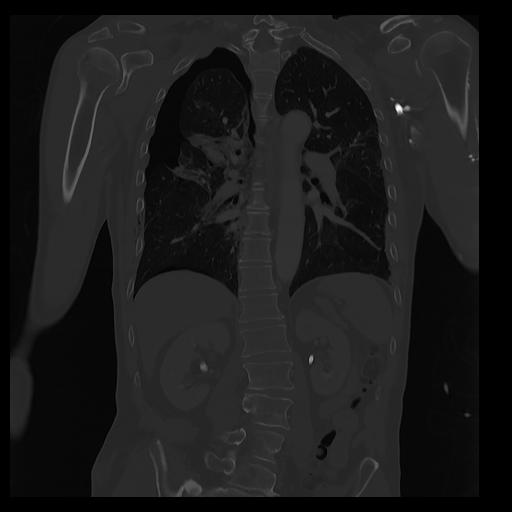

32 PULMON,CE,Coronal,3.000,PULMON,Coronal,